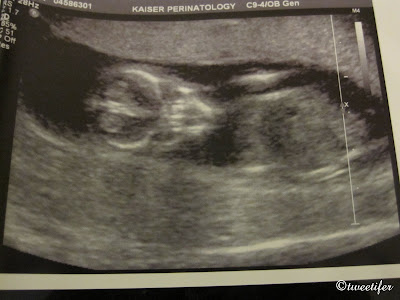

Just wanted to announce our exciting news, we are expecting a baby boy in 2010! Here are his first pictures:

At 19 weeks (waving hi):